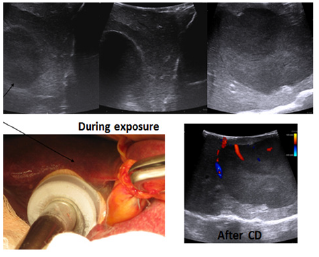

There were 21 women, 26 men. The median age was 56.3 + 4.5 years. The size of the tumors in the liver was 1.5 - 9 cm, the number of tumors - from 1 to 10 (4±3). The target temperature: -186ºС. Exposure time: 3-5 min. During the operation, ultrasound monitoring of the effectiveness of the procedure was used (Figure 1). Radiofrequency ablation (RFA) in a combination of cryo destruction was performed in 3 patients, Cryo + liver resection - in 7, a combination of liver resection + RFA + Cryo - in 5 patients. Open intraoperative RFA and percutaneous RFA were performed in 20 patients, combination of liver resection and RFA in 16 patients.